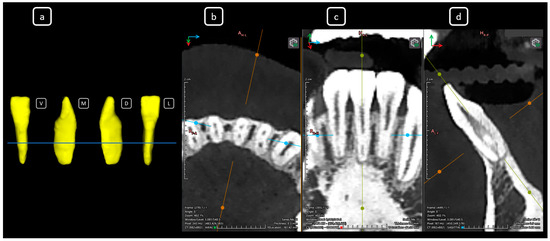

Cone beam computed tomography (CBCT) is a valuable diagnostic tool for evaluating the upper airway and maxillofacial region. This report demonstrates the clinical value of CBCT in identifying significant anatomical variations in endodontics, incidentally detected on a non-endodontic CBCT scan. A 23-year-old female patient underwent CBCT imaging at the Faculty of Dentistry-UJED to evaluate her upper airway. CBCT imaging revealed a unique, complex, and unusual anatomy of mandibular root canals, characterized by Vertucci’s type III root canals in the anterior sextant and co-occurrence of bilateral C-shaped mandibular second molars (type C2 according to Fan’s classification). No therapeutic interventions were initiated due to the patient’s asymptomatic status. CBCT imaging is a valuable tool for integrated diagnostic approaches, underscoring its role in thorough patient management. The integration of multidisciplinary interpretation of CBCT data can enhance diagnostic accuracy and optimize patient records and management, emphasizing the importance of collaborative efforts between radiologists, clinicians, and endodontists. Documenting and sharing such findings can increase awareness of rare anatomical variations, facilitating detection and contributing to medical knowledge. Full article

Figure 1